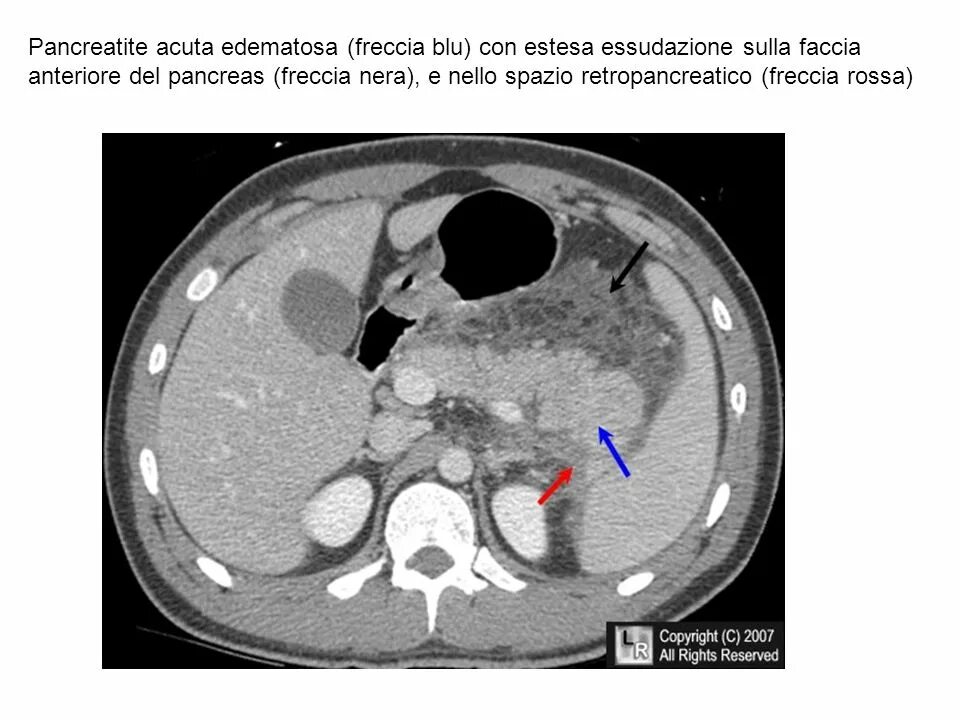

Инфильтрация паранефральной клетчатки на кт. параколитическая клетчатка кт. парапанкреатическая клетчатка инфильтрирована. перипанкреатический инфильтрат.Кт при остром панкреатите. парапанкреатическая клетчатка. кт диагностика панкреатита. острый отечный панкреатит кт.Парапанкреатическая клетчатка. поддиафрагмальное пространство. внебрюшинное поддиафрагмальное пространство. парапанкреатическая клетчатка инфильтрирована.Парапанкреатическая клетчатка что это значитКлетчатка анатомия. понятие о клетчатке в анатомии. основы клинической анатомии. клетчатка понятие.Парапанкреатическая клетчатка что это значитПарапанкреатическая клетчатка. парапанкреатическая клетчатка инфильтрирована. парапанкреатическая инфильтрация. парапанкреатическая клетчатка дифференцирована.Парапанкреатическая клетчатка что это значитПарапанкреатическая клетчатка что это значитХронический панкреатит на кт. парапанкреатическая клетчатка на кт. кт поджелудочной железы. поджелудочная железа на рентгенограмме.Парапанкреатическая клетчатка что это значитПарапанкреатическая клетчатка что это значитПарапанкреатический инфильтрат. парапанкреатическая клетчатка дифференцирована.Парапанкреатическая клетчатка что это значитПарапанкреатическая клетчатка что это значитПарапанкреатическая клетчатка поджелудочной железы. отек парапанкреатической клетчатки. парапанкреатическая инфильтрация. острый деструктивный панкреатит кт.Парапанкреатическая клетчатка что это значитПарапанкреатическая клетчатка что это значитПарапанкреатическая клетчатка что это значитПарапанкреатическая клетчатка что это значитПарапанкреатическая клетчатка что это значитПарапанкреатический инфильтрат. перипанкреатический инфильтрат. парапанкреатическая псевдокиста на кт.Парапанкреатическая клетчатка что это значитПарапанкреатическая клетчатка что это значитПарапанкреатическая клетчатка что это значитПарапанкреатическая клетчатка что это значитПарапанкреатическая клетчатка что это значитПарапанкреатическая клетчатка что это значитПарапанкреатическая клетчатка что это значитПарапанкреатическая клетчатка что это значитПарапанкреатическая клетчатка что это значитПарапанкреатическая клетчатка поджелудочной железы. перипанкреатический инфильтрат. осложнения острого панкреатита презентация. перипанкреатическая клетчатка.Парапанкреатическая клетчатка что это значитКисты и свищи поджелудочной железы. инфильтрация парапанкреатической клетчатки. истинные кисты поджелудочной железы классификация. парапанкреатическая клетчатка поджелудочной железы.Парапанкреатическая клетчатка что это значитПарапанкреатическая клетчатка что это значитПарапанкреатическая клетчатка что это значитПарапанкреатическая клетчатка что это значитПарапанкреатическая клетчатка что это значитПарапанкреатическая клетчатка что это значит